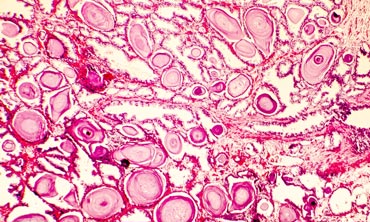

Liegt bei Ihnen der Verdacht eines Prostatakarzinoms vor – z. B. wegen eines abgesicherten erhöhten PSA-Wertes oder eines auffälligen Tastbefundes? Dann muss in der Regel eine systemische Prostatastanzbiopsie durchgeführt werden. Es kann vorab ein multiparametrisches MRT der Prostata durchgeführt werden. Letzte Sicherheit gibt aber nur die Prostatabiopsie. Im Falle von auffälligen Befunden im MRT wird eine kognitive Fusionsbiopsie durchgeführt, dass heißt, auch speziell aus diesen Befunden werden Proben gewonnen. Die Prostatabiopsie führen wir sonografisch gestützt in örtlicher Betäubung und auf Wunsch auch in leichter Sedierung durch.